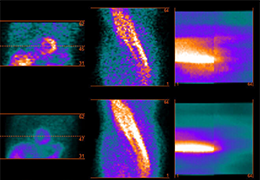

Performs 3D reconstruction and volume rendering.

Multi-planar slicing.

Oblique slicing.